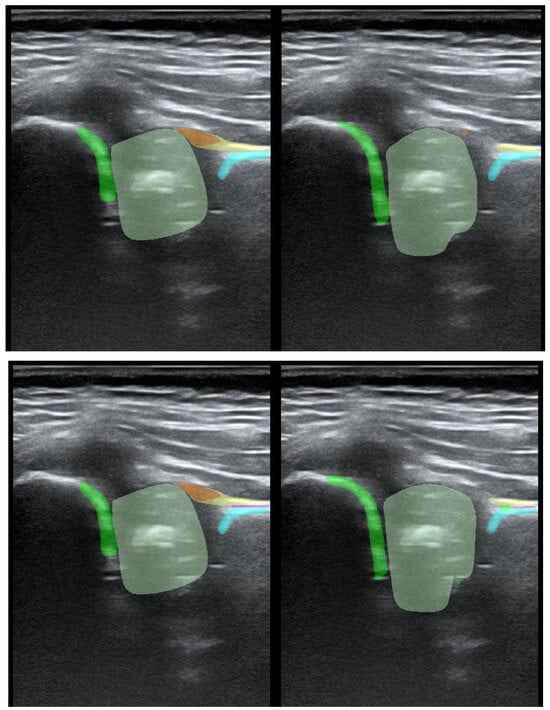

To illustrate the performance of the segmentation model, a comparison is presented between the labels obtained by the segmentation model and the ground truth labels. Two models were analyzed: Model-8 (generating segments for eight classes) and Model-5 (generating segments for five classes). Both the cases with the highest quality model labels and the cases where the model labels were less accurate are presented. Figure 3 shows one of the best cases, in which Model-5 and Model-8 accurately labeled the classes relative to the doctor’s labels. The worst-case scenario was also analyzed, in which the prediction results differ significantly from the ground truth labels (Figure 4).

Figure 3. High-quality model labels (upper—Model-8) and (lower—Model-5). Annotated mask on the left, model mask on the right.

Jcm 14 06332 g003